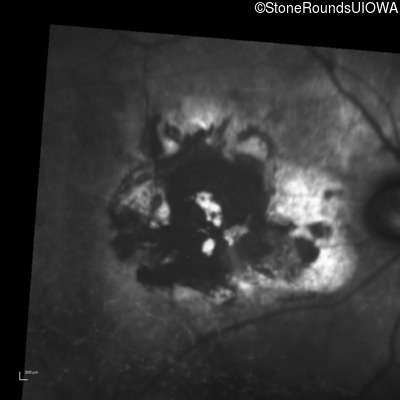

Infrared Fundus Photograph - Right - Count Fingers 2'

Exemplar

Infrared Fundus Photograph - Left - Count Fingers 2'